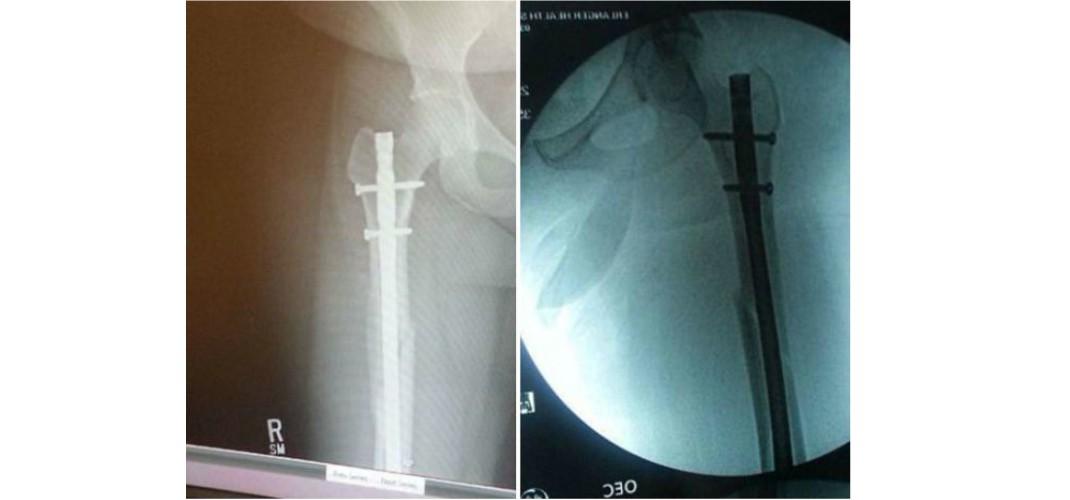

Η Οντρα Τέιτουμ, είναι πλέον άτομο με αναπηρία η οποία προκλήθηκε μετά από τροχαίο ατύχημα που την άφησε με δύο βίδες στον αστράγαλο, δύο στο ισχίο της, δύο στο γόνατό της και ανίκανη να σταθεί πάνω από τέσσερις ώρες.

Όταν συνέβη το ατύχημα, ο αερόσακος κυριολεκτικά εκτόξευσε το πόδι στο πρόσωπο της, σπάζοντας τον αστράγαλο, τη μύτη και το μηριαίο οστούν σε τέσσερις θέσεις.

«Ο αερόσακος άνοιξε και πέταξε το πόδι στο πρόσωπό μου, με αποτέλεσμα να σπάσω τη μύτη μου», είπε. «Έβλεπα το κάτω μέρος του ποδιού μου να κοιτάζει προς τα πάνω. Βασικά ολόκληρη η δεξιά πλευρά μου ήταν σπασμένη, και αυτό συνέβη λόγω της άγνοιας μου. Δεν είμαι ο Σούπερμαν. Δεν θα μπορούσα να πάρω το πόδι μου εγκαίρως».

Γράφει λοιπόν σε ποστ στο Facebook: «Πριν από δύο χρόνια ένας άντρας με κλεμμένο αυτοκίνητο μπήκε μπροστά μας. Ήμουν συνεπιβάτης. Τον χτυπήσαμε με περίπου 70 χλμ / ώρα. Το πόδι μου ήταν στο ταμπλό. Ο αερόσακος άνοιξε ... το πόδι μου έσπασε τη μύτη μου. Η μύτη έσπασε τον αστράγαλο. Το μηριαίο οστό έσπασε σε 4 κομμάτια. Και ο βραχίονάς μου έσπασε προσπαθώντας να σταματήσω την πρόσκρουση. Έχω τόσες βίδες και λάμες και είμαι χάλια μέχρι σήμερα!